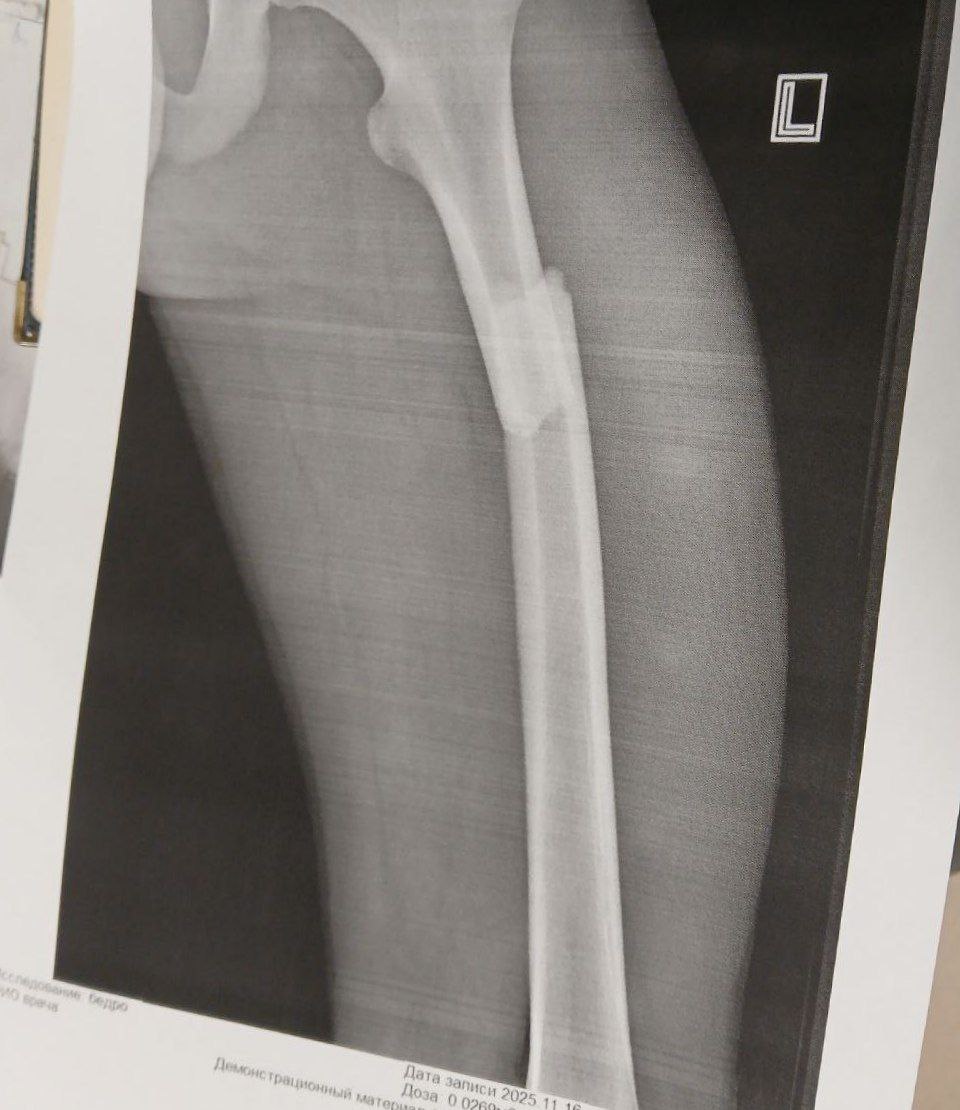

От подписчика из Магнитогорска: Ехал около 60 км/ч, отвлекся на звук цепи буквально полсекунды - обнял столб, сломал бедро (4 фото) 21 ноября 2025 13:40 Источник: